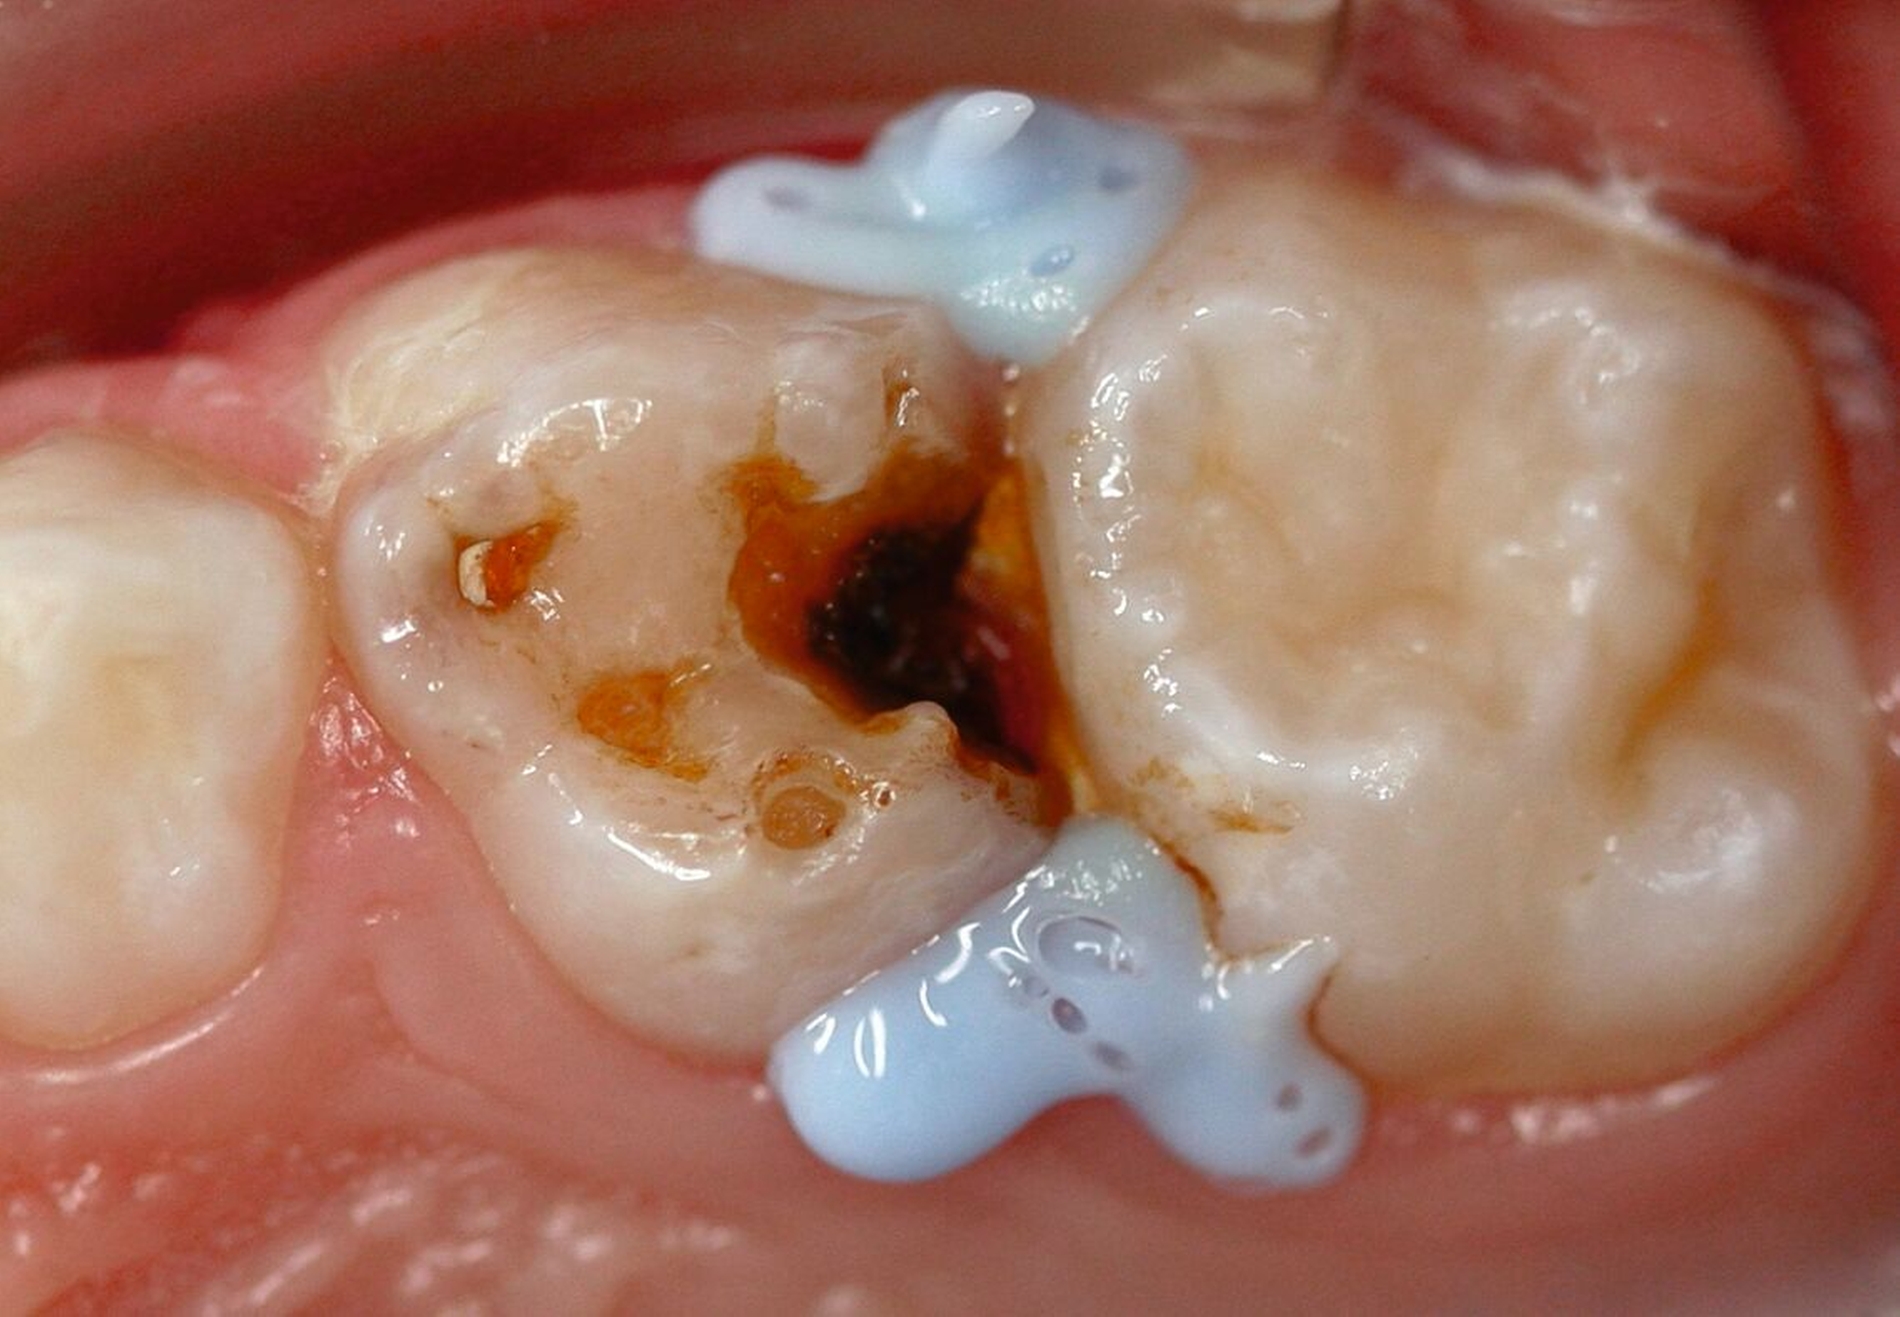

SDF ist besonders wirksam bei der Behandlung von Kariesläsionen (Abbildung 1). Bei der Anwendung auf kariösem Zahnhartgewebe dringen die Silberionen in die bakteriellen Zellwände ein, stören die bakterielle DNA-Synthese und den Stoffwechsel, und führen so zum Zelltod. Zusätzlich stabilisieren die Silberionen die kariösen Läsionen, indem sie die Dentinkanälchen blockieren (Abbildung 2) [Crystal, and Niederman, 2019].

Es ist zu beachten, dass SDF die (Mundschleim-)Haut und die Gingiva vorübergehend verfärben kann, weshalb der Kontakt mit diesen Geweben während der Anwendung vermieden werden sollte (Abbildung 3). Eine Isolierung, zum Beispiel mit flüssigem Kofferdam, ist eine Option (Abbildung 4). Da die Mitarbeit der Kinder oft gering ist, sollten zumindest die Lippen vorher mit Vaseline eingecremt werden, um unbeabsichtigte extraorale Verfärbungen zu reduzieren.

Die Applikation von Silberfluorid ist einfach, gut akzeptiert und lindert erfolgreich Überempfindlichkeiten bei MIH, wie Studienergebnisse unserer Arbeitsgruppe zeigen [Ahmed et al., 2023; Ahmed et al., 2024]. Nachteilig ist jedoch die schwer vorhersagbare, aber mögliche dauerhafte Schwarzverfärbung der hypomineralisierten Bereiche. Hier sollte also in Abhängigkeit der Lokalisation und des Schweregrades der Hypersensibilitäten abgewogen werden, ob diese Technik direkt beim Erstbesuch oder gegebenenfalls doch nur bei persistierender Überempfindlichkeit bei einem der Recall-Besuche erfolgen sollte („SMART“ im Recallbesuch) (Abbildung 7). Sofern MIH-Läsionen hauptsächlich approximal liegen oder die MIH-Molaren so stark betroffen sind, dass unabhängig von der Initialbehandlung mittelfristig eine Kronenversorgung (zum Beispiel Stahlkrone) oder sogar eine Extraktion wahrscheinlich ist, wäre die Silberfluoridapplikation aufgrund der schnellen Wirkung eine probate Option - auch als SMART-Technik beim Erstbesuch.